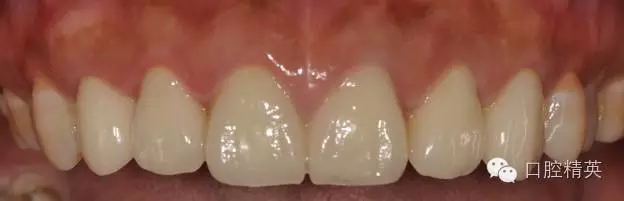

修復(fù)體完成后正面觀

患者發(fā)F音以及下嘴唇干濕線的位置

修復(fù)體完成口內(nèi)照片